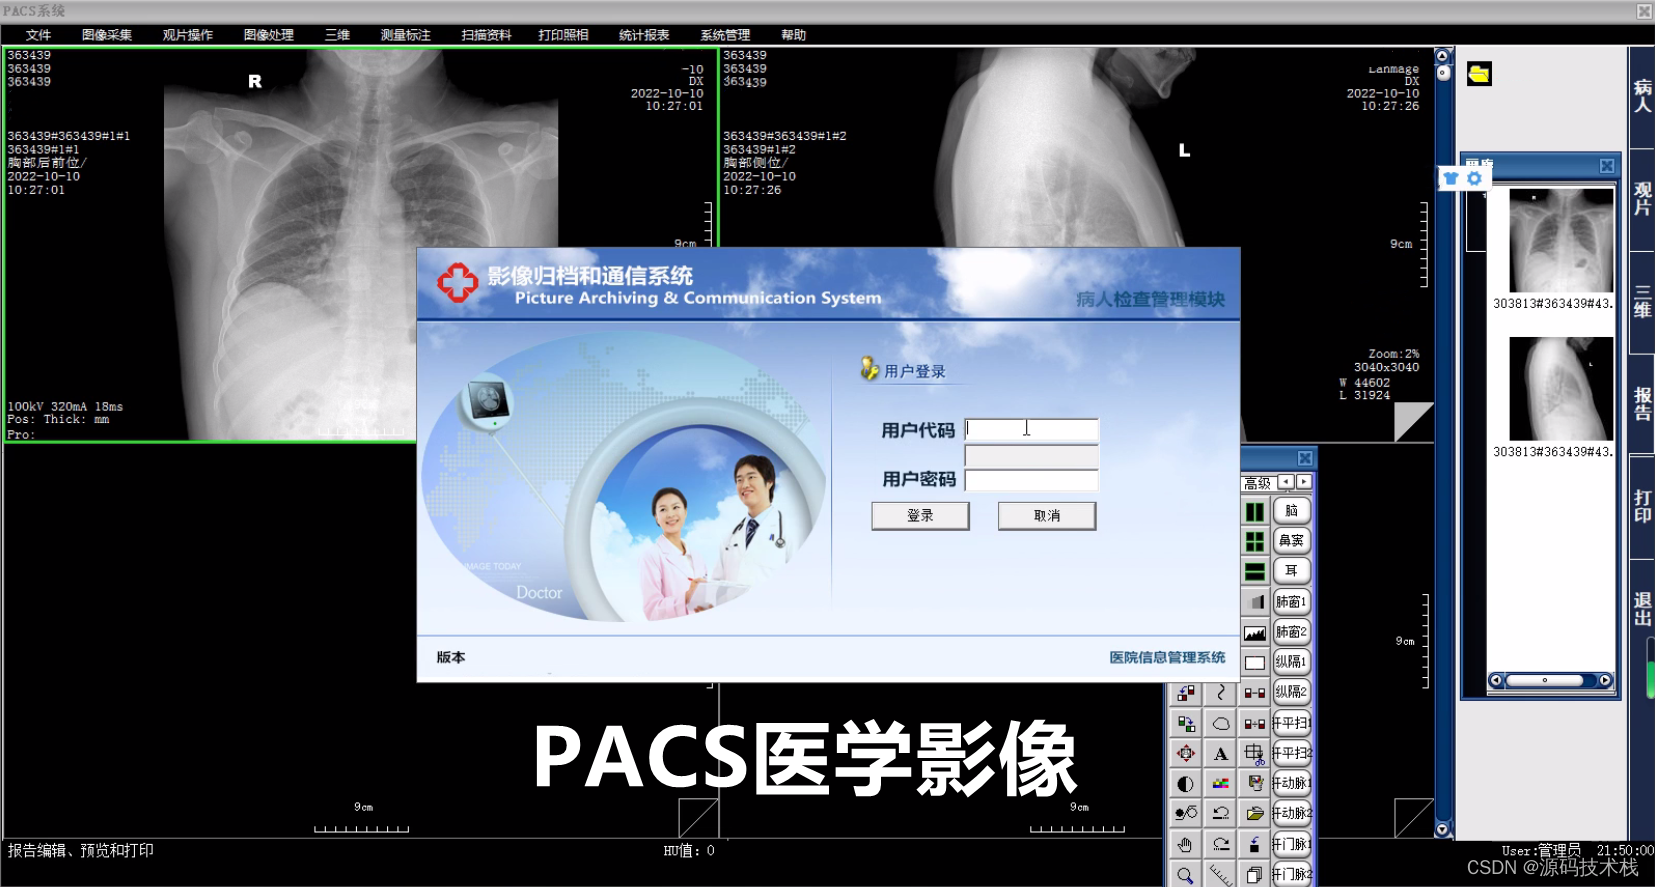

医疗软件中的影像归档与传输系统软件(Picture Archiving and Communication System,简称PACS)是一种用于存储、管理和传输医学影像数据的系统。

PACS是应用在医院影像科室的系统,主要的任务就是把日常产生的各种医学影像(包括核磁,CT,超声,各种X光机,各种红外仪、显微仪等设备产生的图像)通过各种接口(模拟,DICOM,网络)以数字化的方式海量保存起来,当需要的时候在一定的授权下能够很快的调回使用,同时增加一些辅助诊断管理功能。它在各种影像设备间传输数据和组织存储数据具有重要作用。

影像浏览和分析:PACS提供了影像浏览和分析的功能,医生可以在工作站上查看和分析影像,进行病情评估和诊断。同时,PACS还提供了一些辅助功能,如放大、缩小、旋转、对比度调整等,帮助医生更好地观察和分析影像。

安全性和隐私保护:PACS具备一定的安全性和隐私保护机制,确保医学影像数据的安全存储和传输。例如,采用加密技术保护数据的机密性,设置访问权限控制,记录用户操作日志等。